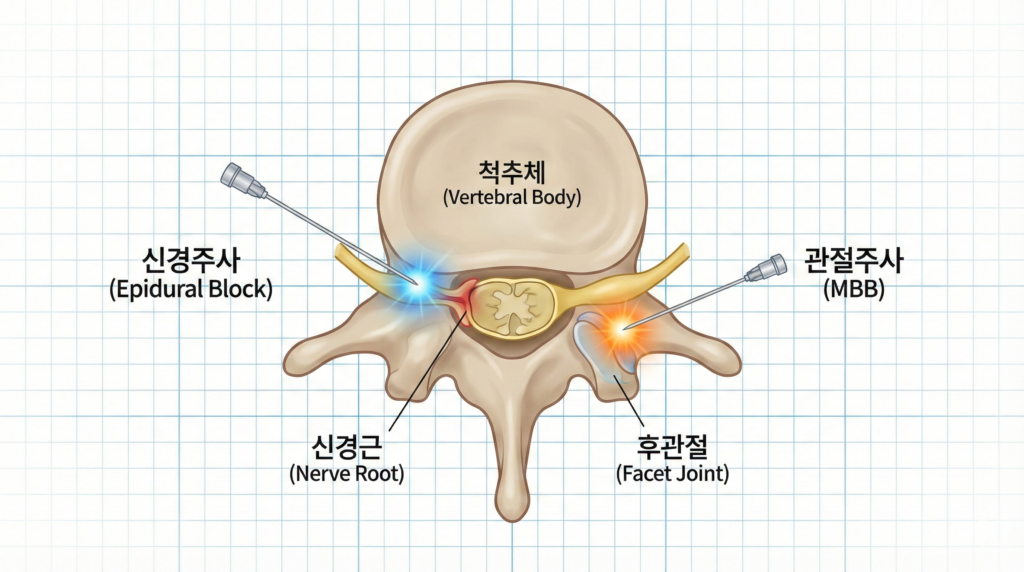

2. 진단이 다르면 치료(주사)도 달라야 합니다

“허리 아프면 무조건 신경주사 맞으면 되나요?”

절대 그렇지 않습니다.

앞서 말씀드린 대로 원인이 다르기 때문에 치료의 타겟도 달라져야 효과를 볼 수 있습니다.

삼덕정형외과는 꼭 필요한 부위에 정확히 주사하는 것을 목표로 합니다.

1) 무릎 아래로 다리가 저릴 때 (신경 문제): 경막외차단술, 신경근 차단술

디스크나 협착증으로 신경이 눌려 다리가 저린 경우에는 눌린 신경 주변의 염증을 가라앉히는 치료가 필요합니다.

이때 시행하는 것이 경막외차단술(신경주사)입니다.

영상 장비(C-arm)를 보며 신경 주변에 정확히 약물을 주입하여 염증을 씻어내고

부종을 가라앉히는 가장 확실하고 효과적인 비수술적 치료법입니다.

이런 경우 근육에만 주사한다면 확실한 치료 효과를 보기 힘들겠습니다.

2) 허리만 뻐근할 때 (관절/근육 문제): 후관절차단술, 후지신경차단술, 근육회복 주사

신경이 눌린 게 아닌데 무턱대고 신경주사를 맞는 것은 큰 의미가 없습니다.

근육의 뭉침에 어느 정도 신경의 영향이 있을 수 있으나 직접적인 치료가 되기는 힘듭니다.

허리 후관절 문제라면 관절 부위에 직접 치료하는 내측지차단술(MBB)이나 후관절차단술(facet block)이 효과적이며

근육이 단단하게 뭉쳐서 생긴 통증이라면 통증 유발점을 찾아 풀어주는 근육회복주사가 훨씬 효과적입니다.